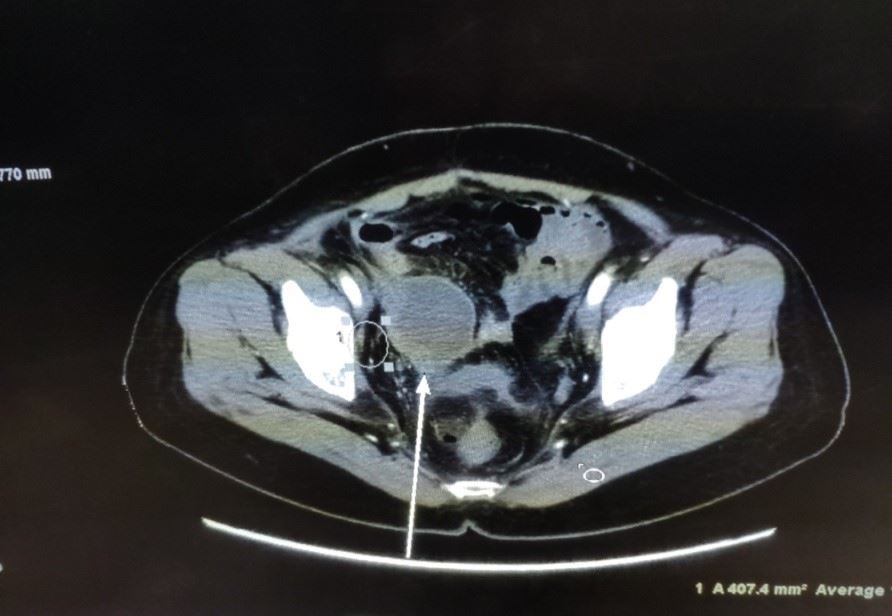

【明慧网二零二三年三月二十三日】二零一八年十月,我的表姑从美国回来就医,她患肝癌十余年,期间多次转移都通过手术切除得以缓解,但这次检查结果很悲观(见图1),是多个脏器的转移,在医院看了肿瘤外科、妇科、胃肠外科、泌尿外科等,各外科专家们均无良策!无奈之下接受了肿瘤内科主任建议的以减轻疼痛为目的的姑息性放疗。

'图1'

图1

在此情况下,我告诉了她大法被迫害的真相,帮她做了三退,并告诉她多念“法轮大法好,真善忍好”。就这样,她开始每天念诵九字真言,一天大约四十五分钟(分次完成)。刚开始时,她头脑中的干扰比较严重,我帮她发正念清除后,她可以比较安静的念诵真言。经过近两个月时间,她的症状大为改善,同时也完成一个疗程的放疗。

之后她回到美国,约半个月后她在国外开始复查,她做了CT、超声、磁共振、PET-CT,所有的检查指示肿瘤病灶完全消失了,她非常的震惊,对我说,她见证奇迹了,她一定要坚持念下去。同时她的美国医生和中国医生都对她的治疗效果表示不可思议,这是她度过的第一个死劫。

结果到二零二零年四月的一天,她突感下腹部剧痛,人也无法站立,家人打120送急诊,经超声检查认为是转移瘤,后又行PET-CT检查,报告显示盆腔有一4.9cmx7.3cm的巨大肿块,同样考虑为转移瘤,外科医生收到报告后表示无法手术了!

更为惊奇的是,医生在做CT增强扫描时发现肿瘤可能出现大面积的坏死(见图2,箭头所指肿瘤的阴影部份),后来对肿瘤进行了穿刺,病理报告证实了,肿瘤中间部份变成了坏死组织和炎症细胞(见图3),而这个肿瘤的表面仍然是肝癌细胞(后补充免疫组化报告)。

'图2'

图2

'图3'

图3

这又是一个天大的奇迹。仅仅五天时间,肝转移瘤居然出现中间大面积坏死现象,肿瘤科主任和PET中心主任均表示肝癌在盆腔的转移瘤在未经治疗的情况下从未见过中间坏死的情况。我想应该是大法的威力让肿瘤坏死。后来表姑做了个射频消融处理了表面的癌细胞,一周后基本恢复正常。